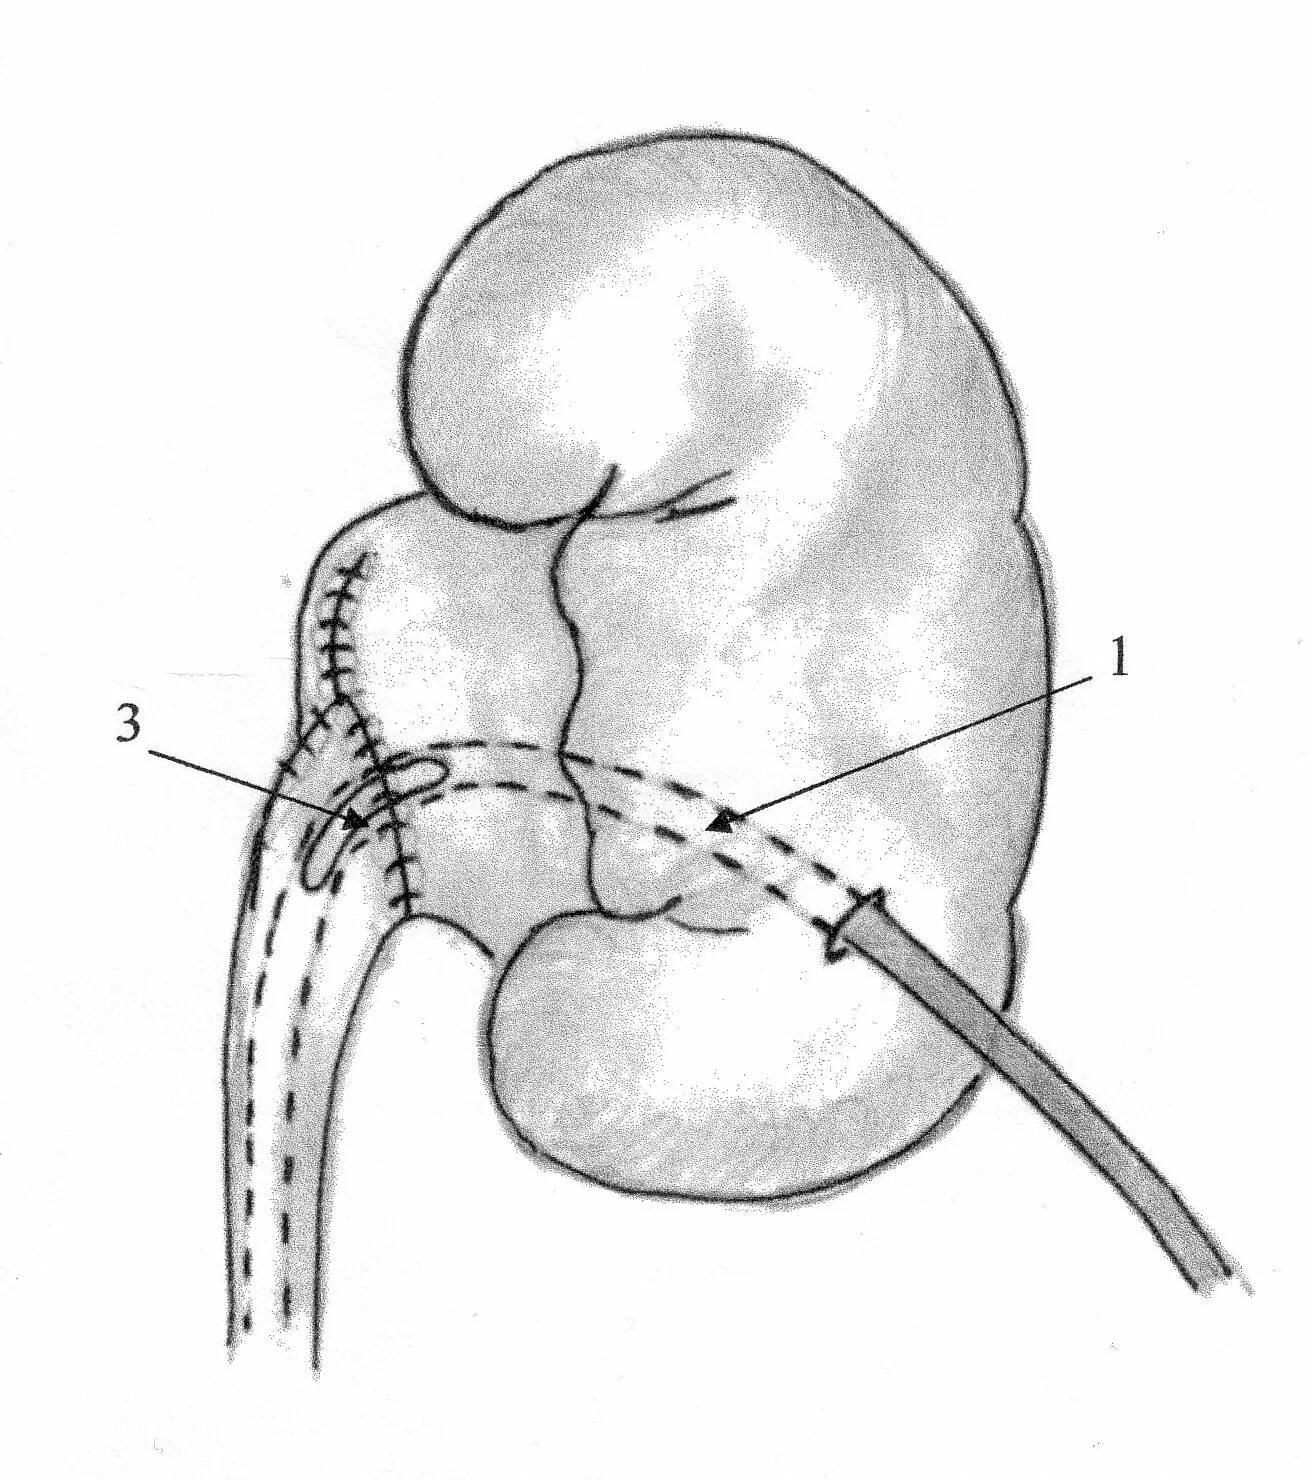

Гидронефроз почки после операции